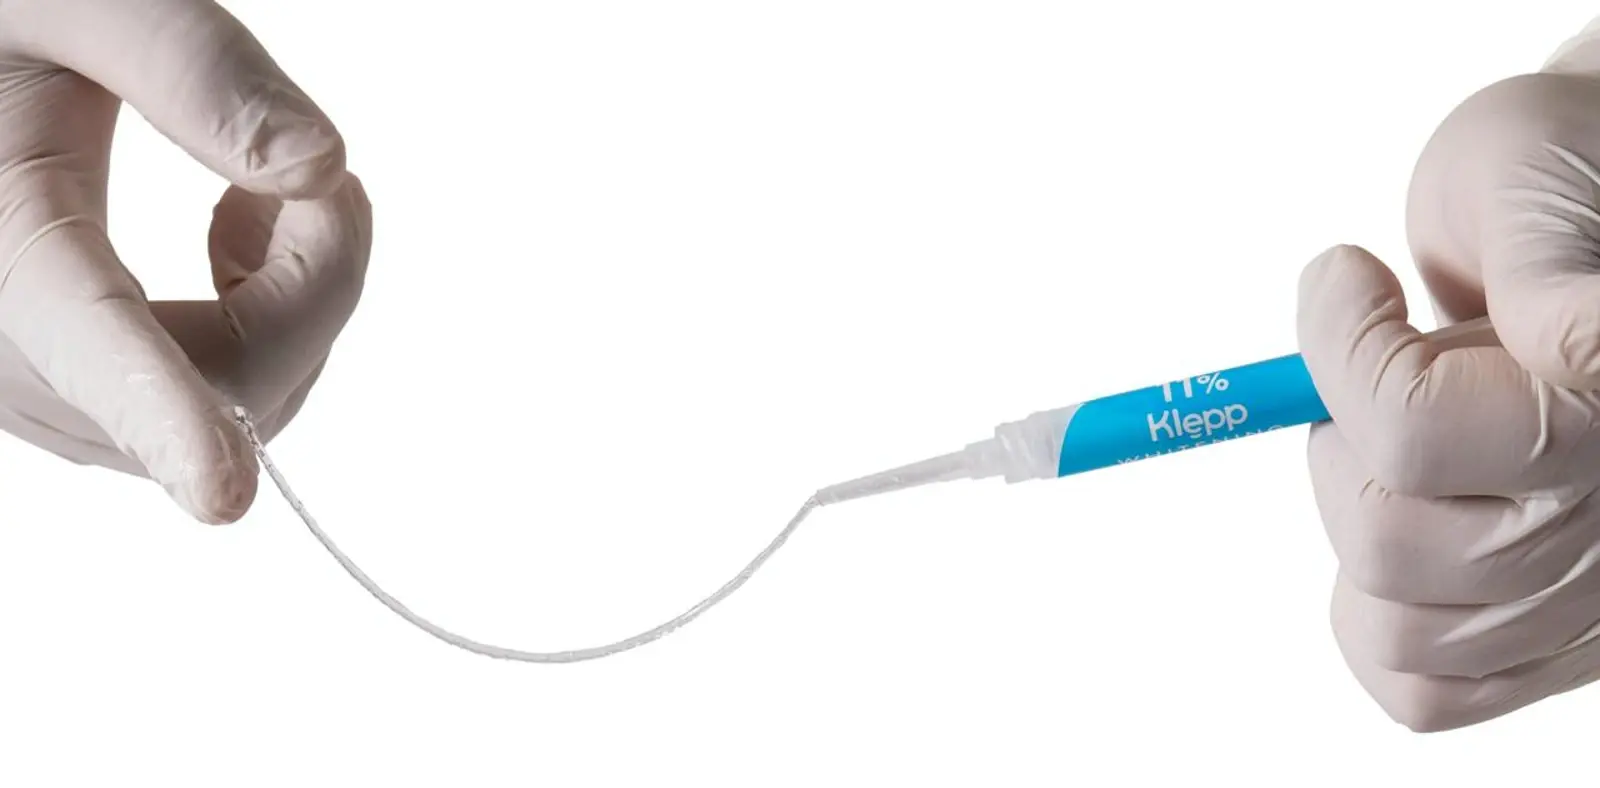

El aclaramiento dental durante el tratamiento con alineadores es eficaz y consigue un tono dental homogéneo, debido a la capacidad de las partículas del agente blanqueador para penetrar las zonas adyacentes a los ataches20,21. Durante varios años hemos colaborado con la empresa Klepp, filial del grupo Grimberg Dentales de Argentina, para crear un gel a base de peróxido de carbamida al 11% para el tratamiento de pacientes con alineadores.

Este producto ha mostrado ser eficaz para mejorar el color dental, disminuir la placa bacteriana y reducir los índices de inflamación gingival. En el seguimiento de casos manejados con alineadores como guardas portadoras del producto Klepp testeados durante un periodo de 4 semanas, hemos observado con el equipo de espectrofotometría Easy Shade de VITA que no tenemos regresiones de color 6 meses después de interrumpir el aclaramiento.